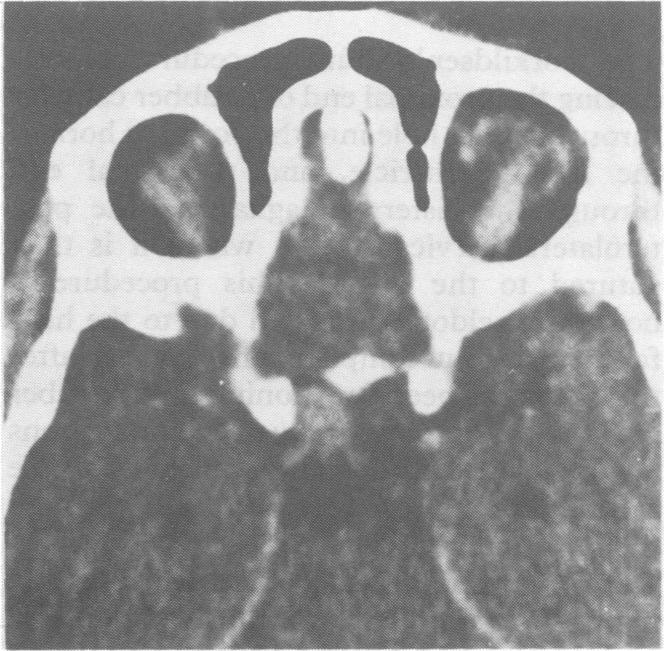

Spontaneous intraneural haematoma of the optic nerve.

J Neurol Neurosurg Psychiatry. 1991 Jul;54(7):653-4. doi: 10.1136/jnnp.54.7.653-a.